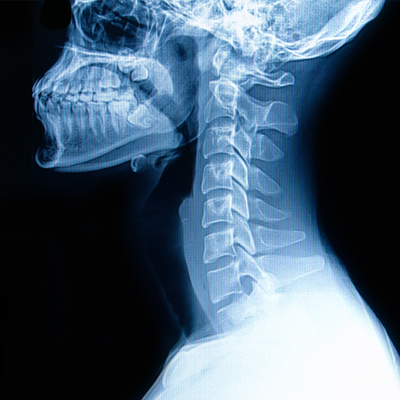

Forward head posture occurs when the head drifts in front of the shoulders instead of stacking naturally over them. This shift changes how weight, tension, and neurological load are distributed through the cervical spine.

A healthy cervical spine has a gentle lordotic curve that allows the head’s weight to be distributed efficiently while protecting spinal joints, discs, and nerves.

When that curve flattens or reverses—often due to sustained forward head posture—several important changes occur:

The cervical curve plays a critical role in how forces move through the spine.

When the neck loses its natural curve:

- Head weight is no longer absorbed evenly

- Stress shifts toward discs, joints, and supporting tissues

- Muscles must work harder simply to hold the head upright

- The spine’s tolerance to daily activities decreases